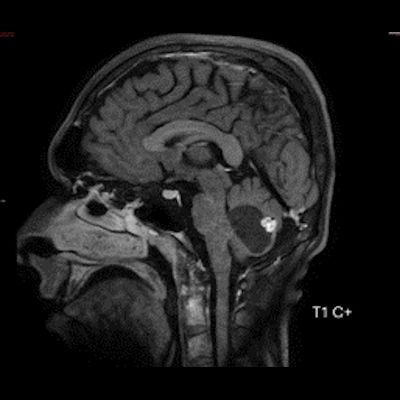

- B) Beyin MRG incelemesinde; 4. ventriküle bası etkisi oluşturan yaklaşık 3.5 cm boyutta, T2A hiperintens T1A hipointens kistik komponent (oklar) ve posteriorunda T1 ve T2A serilerde parankim ile izointens, içerisinde flow void alanların (oklar) izlendiği, post kontrast görüntülerde yoğun kontrast tutulumu gösteren mural nodül (oklar) barındıran düzgün sınırlı lezyon izlenmektedir.

- Kistik komponent: T1A hipointens, T2A hiperintens

- Mural nodül: T1A izo-hipointens, T2A orta derecede hiperintens olabilir.

- Kontrastlı incelemelerde mural nodül belirgin ve yoğun kontrast tutulumu gösterir. Ancak kist duvarında genellikle kontrastlanma beklenmez.

- T1 ve T2A görüntülerde flow voidler sıktır.